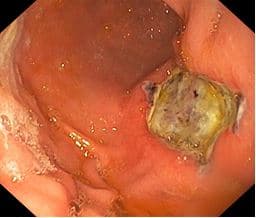

При контрольном осмотре через сутки определяется язва - струп под налетом фибрина, без признаков кровотечения, дополнительная коагуляция не потребовалась.

На рисунке: Первые сутки, контрольный осмотр.